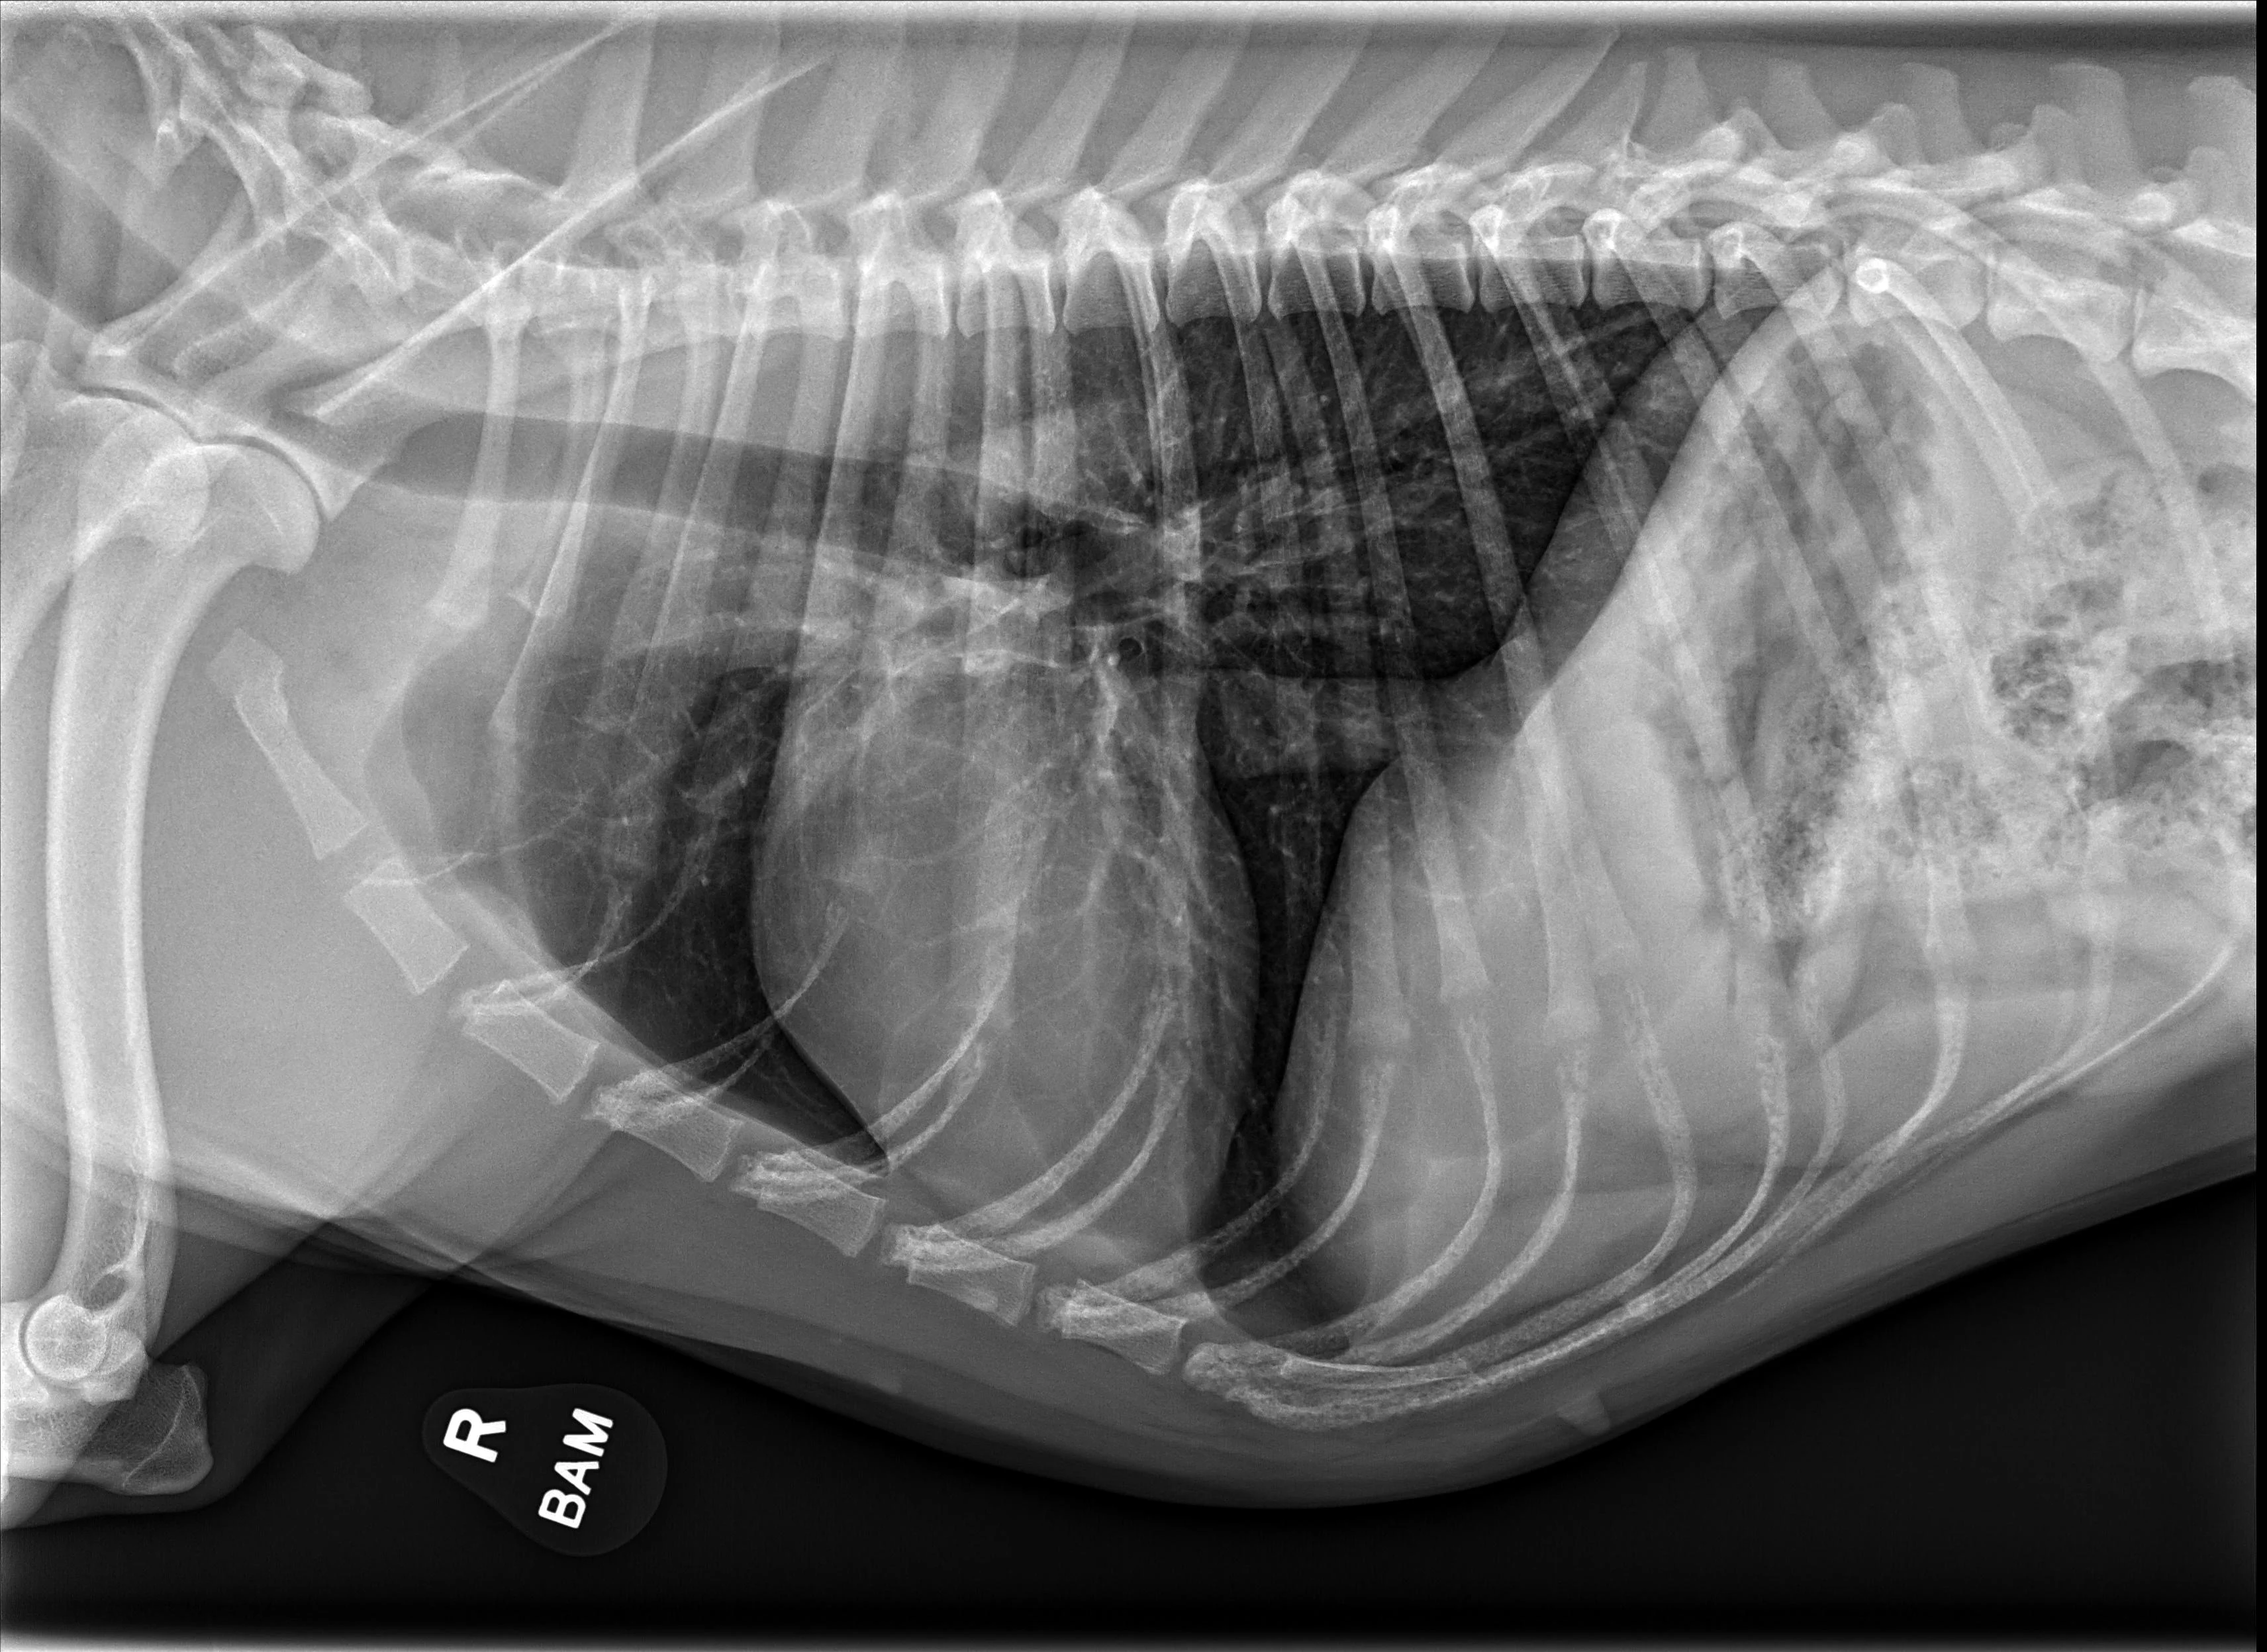

A subset of patients with acquired heart disease may develop left-sided congestive heart failure (CHF). In addition to left-sided cardiomegaly, dogs with active CHF secondary to MMVD commonly exhibit lobar pulmonary venous enlargement on radiographs, as well as an interstitial to alveolar radiographic lung pattern that typically develops in the perihilar region and right caudal lung lobes (Figure 8); however, in dogs with DCM, this lung pattern may be seen in the ventral lung lobes (Figure 9). The radiology lung score is an objective method to quantify severity but was not associated with the recurrence of CHF or survival in one study.16 Dogs administered diuretics may not have pulmonary venous dilation, and some dogs with CHF secondary to acute increase in left atrial pressure (eg, aortic valve endocarditis, chordae tendineae rupture) may not have significant cardiomegaly.

FIGURE 8 DV (left) and left lateral (right) projections consistent with left-sided CHF in a dog with advanced MMVD. Pulmonary venous distention (arrowheads), an interstitial to alveolar pattern in the perihilar region extending caudodorsally, cardiomegaly, and aerophagia are present. VHS, VLAS, M-VLAS, and VRHi collected from the left lateral view are 10.9, 2.8, 4.8, and 3.2, respectively.